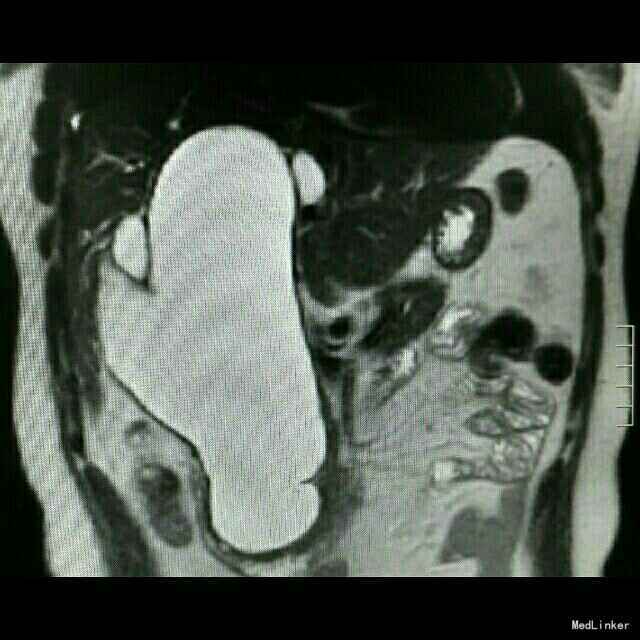

查体:皮肤巩膜轻度黄染 检查:B超示胆总管囊性占位,胆囊增大,肝内胆管扩张。MRCP:先天性肝外胆管囊肿,伴肝内胆管及胰管扩张,胆囊炎,右肝血管瘤可能。TB 65 umol/L;DB 41 umol/L; ALT 137U/L;AST74 U/L ;γ-GT366 U/L术后恢复正常。肿瘤指标正常。

诊断:先天性胆总管囊肿,慢性胆囊炎。 治疗:行胆总管囊肿切除+胆囊切除+胆道空肠Roux-en-y吻合术。术中腹腔未见积液,胆总管大小越25*8.5cm,囊壁较厚,胰头部受压明显,胆囊10*6*5cm。沿胆囊底打开胆囊浆膜,逆行游离至胆囊管汇入处,结扎胆囊动脉,打开肝十二指肠韧带,沿胆总管囊肿游离囊肿,保护肝动静脉及门静脉,向下游离至胰内胆管,于囊肿下端切断胆总管,结扎残端。向上游离至肝门部,于左右肝管汇合处离断,完整切除囊肿。距屈氏韧带25cm直线闭合器断空肠,游离远端空肠系膜行肝总管远端空肠段侧吻合。距胆肠吻合口远端45cm处,空肠与近端空肠残端以直线切割闭合行空肠侧侧吻合。间断缝合残端,吻合口放置引流管,关腹。术后加强白蛋白对症支持治疗,术后第5日开始进食流质。病理回报慢性胆囊炎。